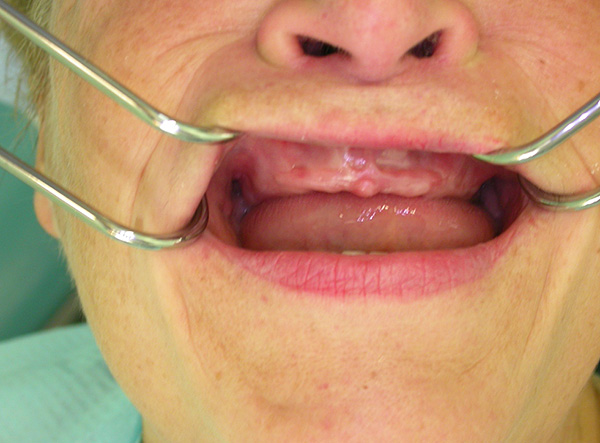

Mito 5: às vezes, os implantes são rejeitados e, quando são rejeitados, ocorre gangrena da mandíbula.

De fato, mesmo que o implante não tenha sido instalado corretamente e o médico tenha cometido muitos erros, a gangrena da mandíbula não se desenvolve. No pior dos casos, ocorre inflamação e supuração na zona de implantação, o implante se torna móvel e rejeitado. É impossível não perceber isso, e a dor nos estágios iniciais simplesmente força o paciente a consultar um dentista novamente.

A foto abaixo mostra os implantes removidos da mandíbula:

Nas pequenas situações em que, por alguns motivos, dependendo ou não do médico, os implantes instalados na mandíbula são rejeitados, ocorre uma diminuição banal no tecido ósseo. Essa diminuição óssea no futuro pode ser facilmente compensada por sua restauração artificial usando um enxerto ósseo.